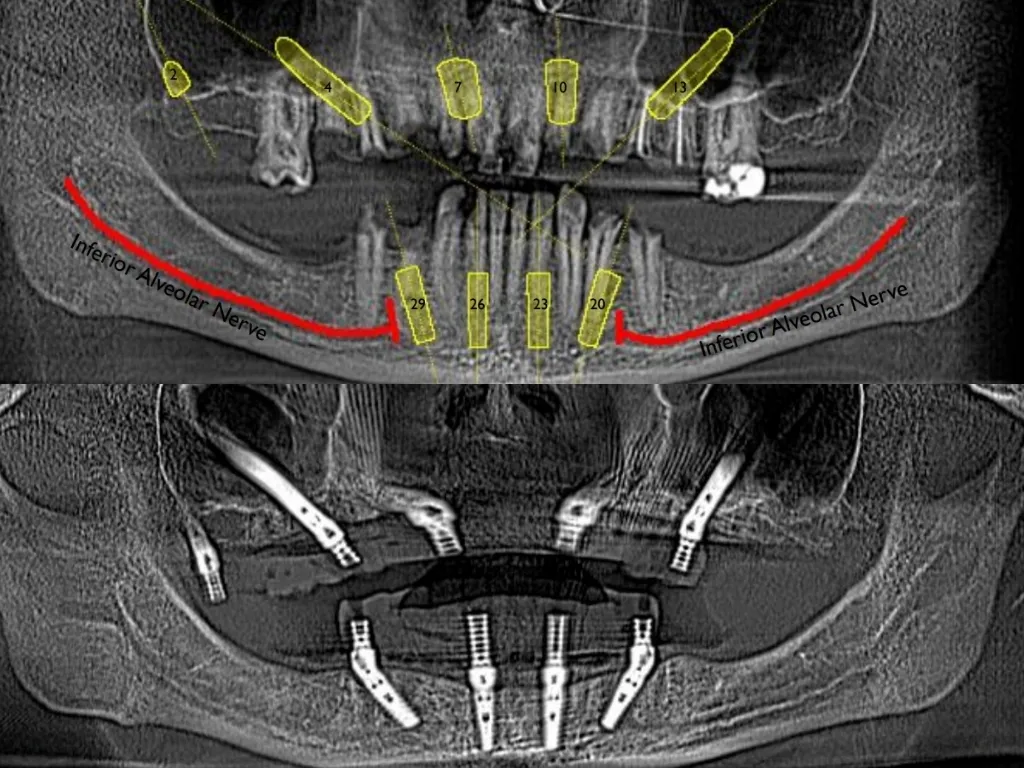

vaka_img

İmplantın Üstüne Kemik Yürümesi

Dr. Edward Shapiro